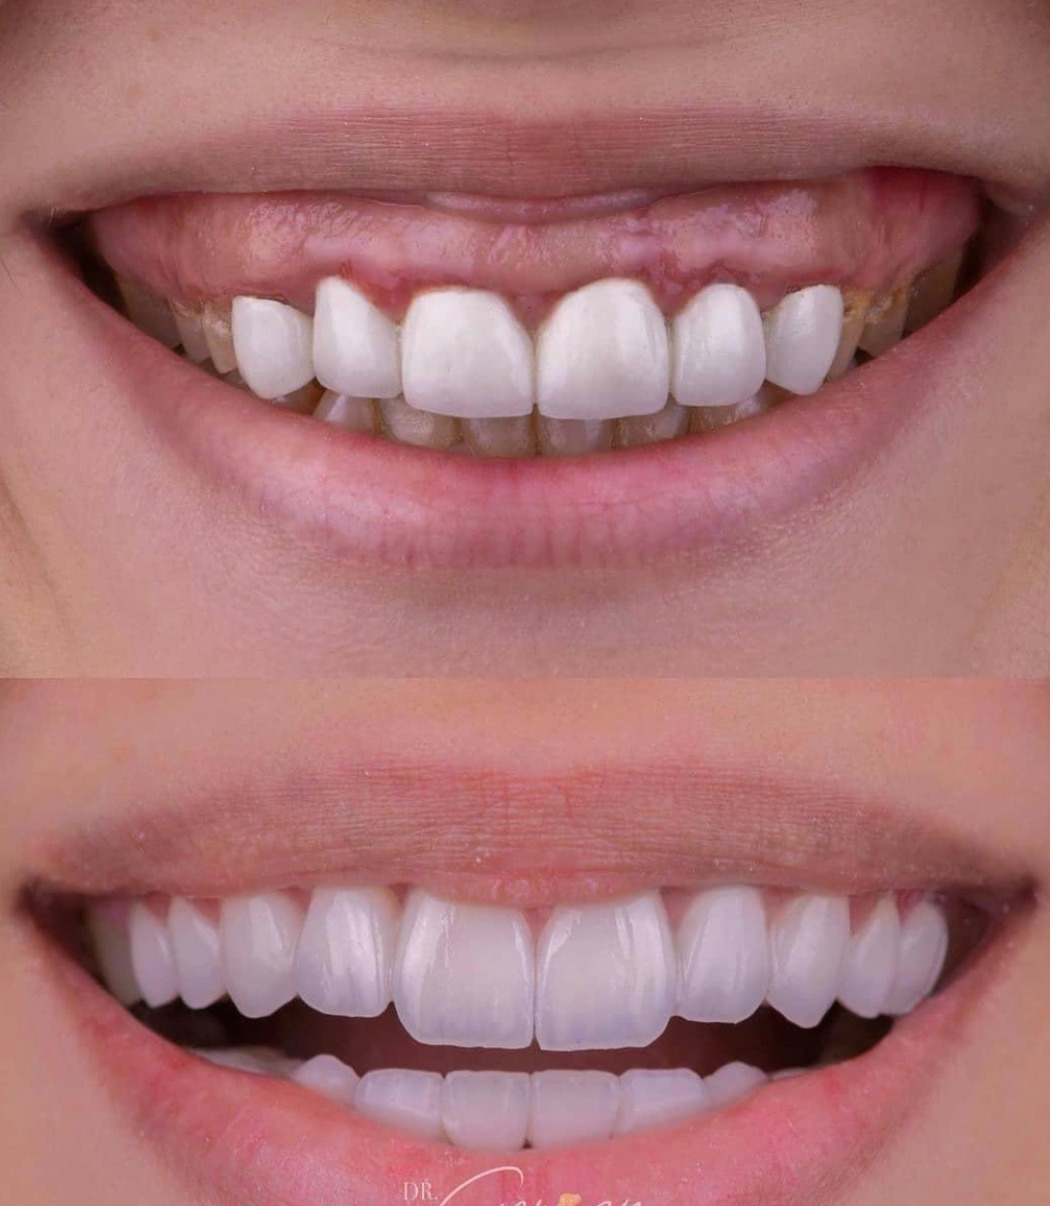

• 症例1:審美治療の治療前と、治療後